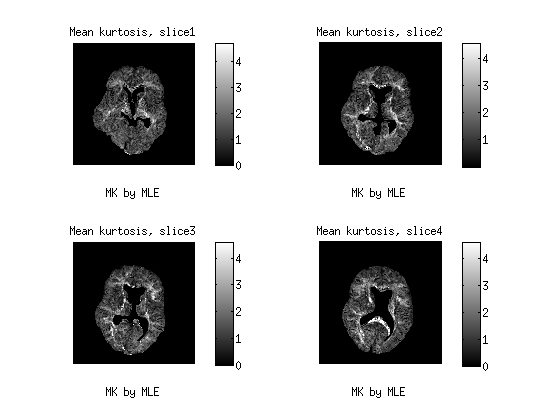

4.2 Real data

This data are part of a real experiment. It is consist of 2204 diffusion MR-images of the brain from an healthy human volunteer, taken from four 5mm5𝑚𝑚5mm-thick consecutive axial slices, and measured by a Philips Achieva 3.03.03.0 Tesla MR-scanner. The image resolution is 128×128128128128\times 128 pixels of size 1.875×1.8751.8751.8751.875\times 1.875 mm2𝑚superscript𝑚2mm^{2}. After masking out the skull and the ventricles, we remain with a region of interest (ROI) containing 187641876418764 voxels. In the protocol, we used all the combinations of the 323232 gradient directions with the b𝑏b-values varying in the range 0, 62, 249, 560, 996, 1556, 2240 s/mm2𝑠𝑚superscript𝑚2s/mm^{2} , with 333 repetitions, for a total of 7 242 904 data points.

In this session, we depict the results by MD Fig. 3, FA Fig. 4 as well as MK Fig. 5 from the proposed CWLS and MLE methods.The diffusion weighted MR data is in the range of (0, 581), acquired by 32 distinct gradient directions with seven different b values. After comparison, we can see that the image constrasts by the MLE method gain much more detailed structural information, especially in Fig.4 and Fig. 5 than those by the CWLS in the same scales.

Figure 5: 3d maps of MK by the CWLS and the MLE methods from four consecutive slices of human brain. The MK maps were scaled in the range of (0,4).